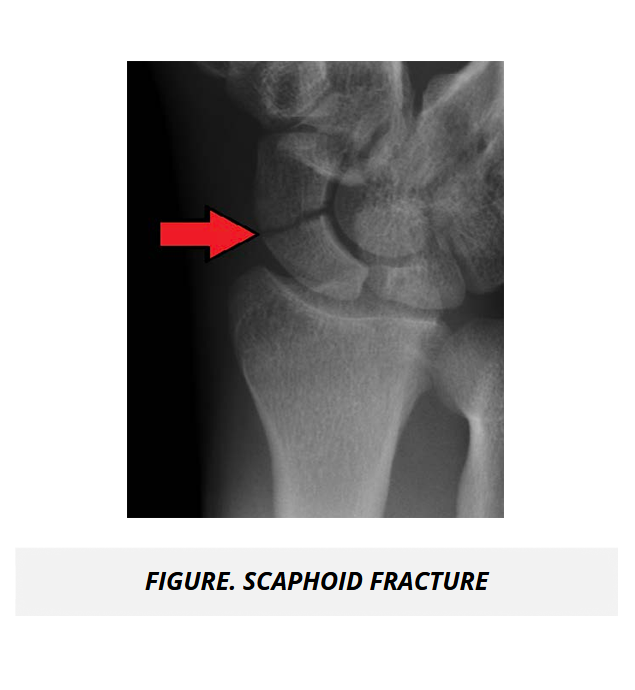

The UMock USMLE® Step 1 prep course features high quality pathologic images, gross and microscopic views, as well as radiologic imaging illustrating key concepts, disorders, and abnormal processes to help you gain a complete understanding of subject material.

The course features detailed tables and high quality radiologic and gross images to help you conceptualize the application of medicine for normal and abnormal body system processes and pathologies in rheumatology and the musculoskeletal system.

In Anatomy, the UMock USMLE® Step 1 prep course presents the most important high-yield facts you need to memorize for the exam, and helps you understand and apply clinical correlations of the structure and organization of the body to clinical scenarios such as fractures, trauma, and injuries. The course is illustrated with high quality descriptive images of anatomic relationships to further enhance your ability to apply knowledge to concepts.